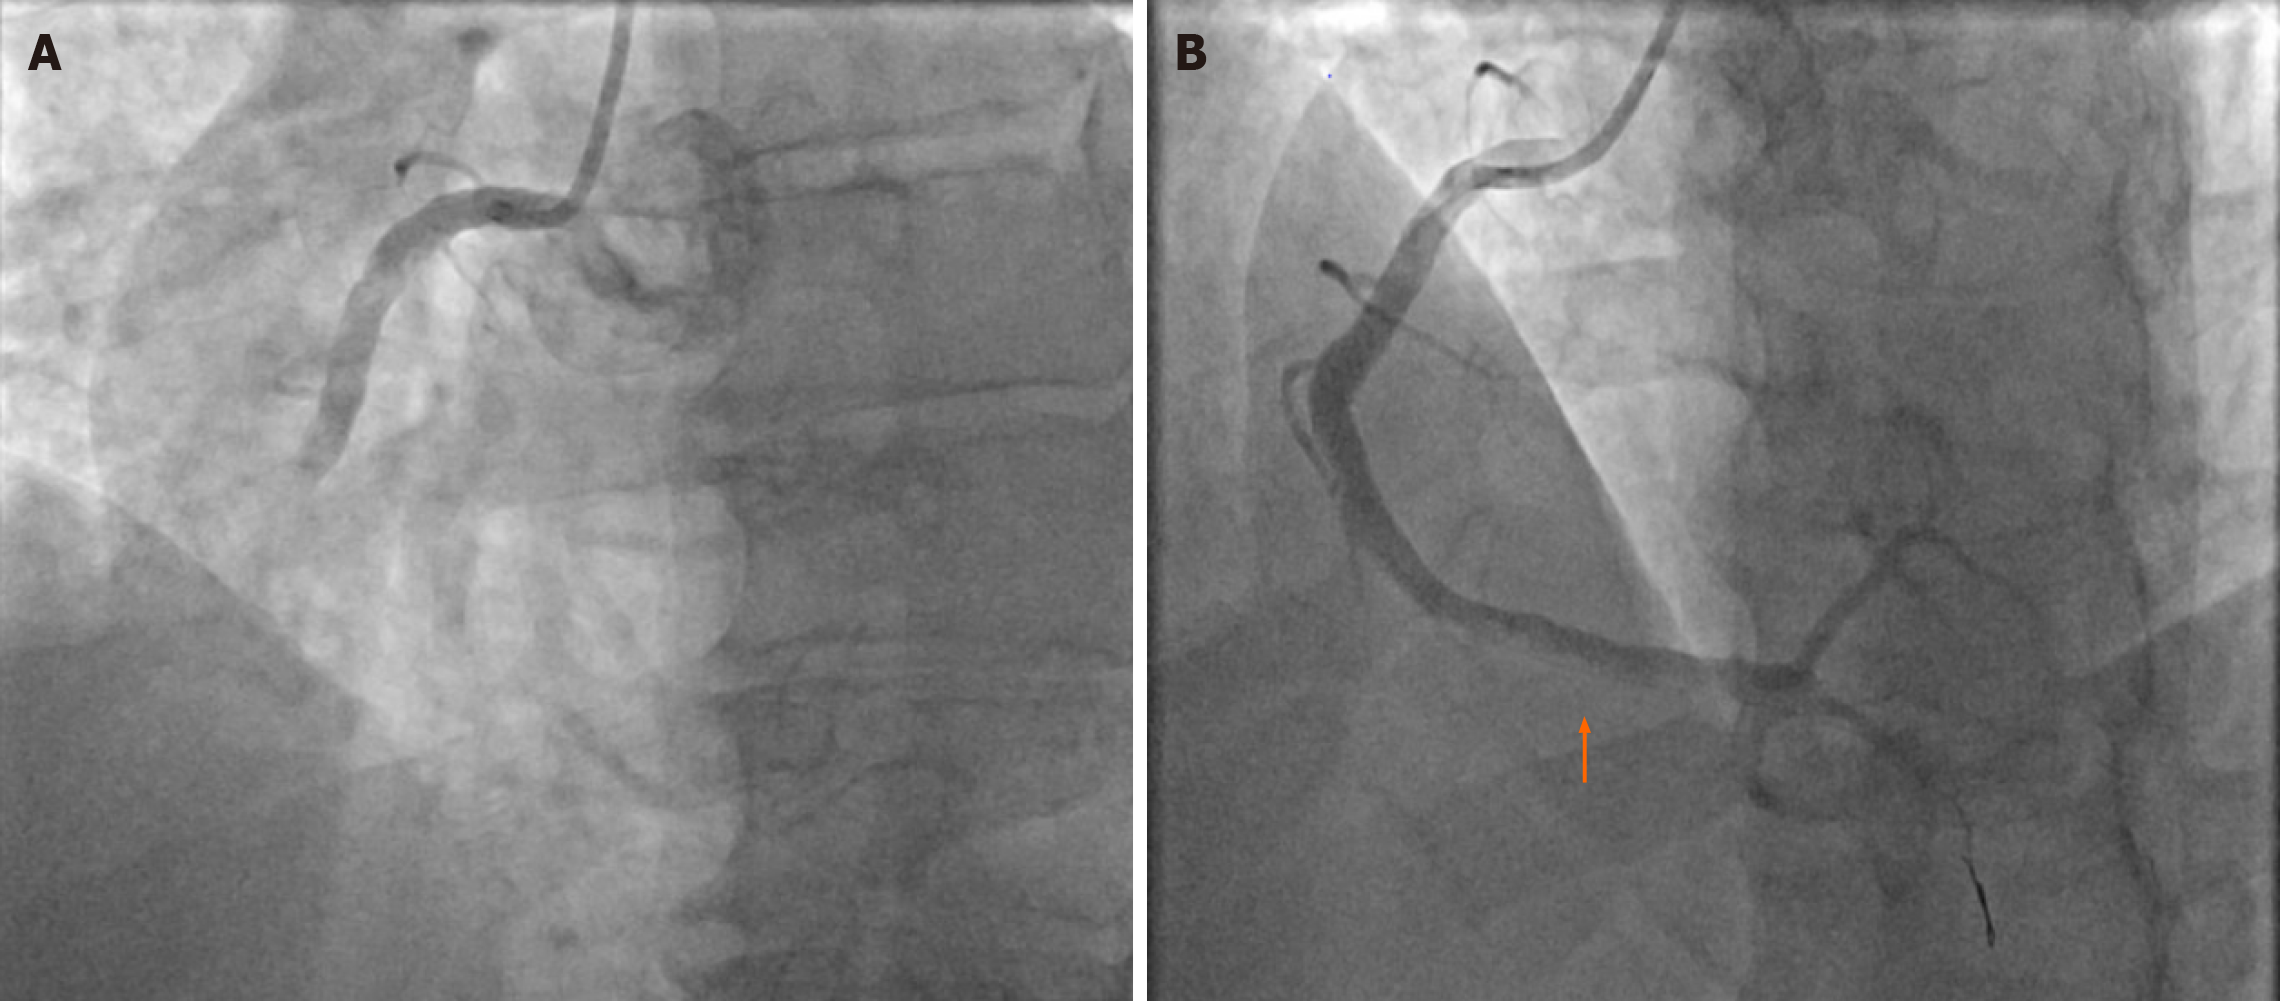

Finally, the efficacy of current manual thrombectomy catheters has been questioned recently[52,53]. Manual thrombectomy devices have relatively small crossing profiles ranging from 0.065 to 0.068 inches, and both angiographic and imaging data suggests that these catheters often leave behind large residual thrombus burden (rTB)[52] (Figures 1 and 2). This rTB would inevitably increase the risk of distal embolization and NRP and maybe linked to worse clinical outcomes. In fact, data from the TOTAL trial highlighted that one-third of patients had large rTB despite manual thrombectomy[52]. More importantly, this group had a significantly higher risk—over 80% increase—in MACE, including higher cardiovascular death[52,53]. Therefore, better and more effective thrombectomy tools are needed to appropriately address the concept of TA in patients presenting with STEMI.

Figure 2

Figure 2 Large residual thrombus burden despite multiple thrombectomy attempts. Filling defect (orange arrow) within the distal right coronary artery segment, despite multiple thrombectomy runs. A: Shows the angiogram picture before wiring, mid blocked with high thrombus burden lesion; B: Showed large amount of residual thrombus at the distal right coronary artery despite multiple thrombectomy attempts.